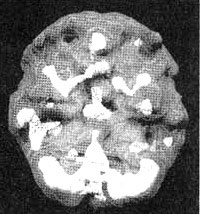

Мозг Линды. Результаты сканирования SPECT

Трехмерное изображение — активный мозг, вид сбоку.

До лечения: обратите внимание на выраженное усиление активности в поясной системе, в базальных ганглиях и в лимбической системе.

После лечение зверобоем. Активность в поясной системе, в базальных ганглиях и в лимбической системе нормализовалась.

Когда Линда пришла ко мне на прием, ей было 26 лет. Два раза она подвергалась жестокому изнасилованию, ее любовник был садистом, а сама она подростком пережила смерть многих своих друзей. Она страдала от депрессии, тревоги, беспокойства и наркотической зависимости. На первом сканировании SPECT мы обнаружили повышенную активность поясной системы (трудности с переключением внимания), базальных ганглиев (тревога) и лимбической области (депрессии и неконтролируемые настроения). После четырех сеансов с использованием техники десенсибилизации и коррекции переработки информации с помощью движений глазных яблок (EMDR) — специального метода коррекции, применяемого для лечения после травмирующих событий, и одного месяца приема зверобоя (по 900 мг в день), Линда почувствовала себя значительно лучше. Повторное сканирование выявило нормализацию активности во всех.